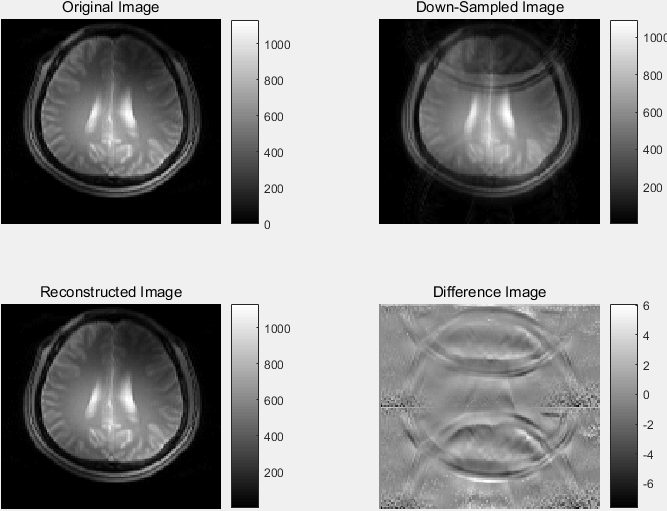

汇总对比显示:

%% Summary

对欠采样重建图像与全采样重建图像作差并显示:

%% Compute difference image

显示 RSOS 重建 MR 图像:

显示恢复的各线圈及 RSOS 重建的相位角图像:

6. 欠采样 k 空间数据 IFFT 转换到图像域并显示

dsImage 是通过 平方和根 (root-sum-of-square) 方法 组合 所有线圈各自的欠采样 MR 复数值图像数据 dsBrainCoils 而重建的 总体欠采样 MR 实数值图像,size = 120×128,type = double